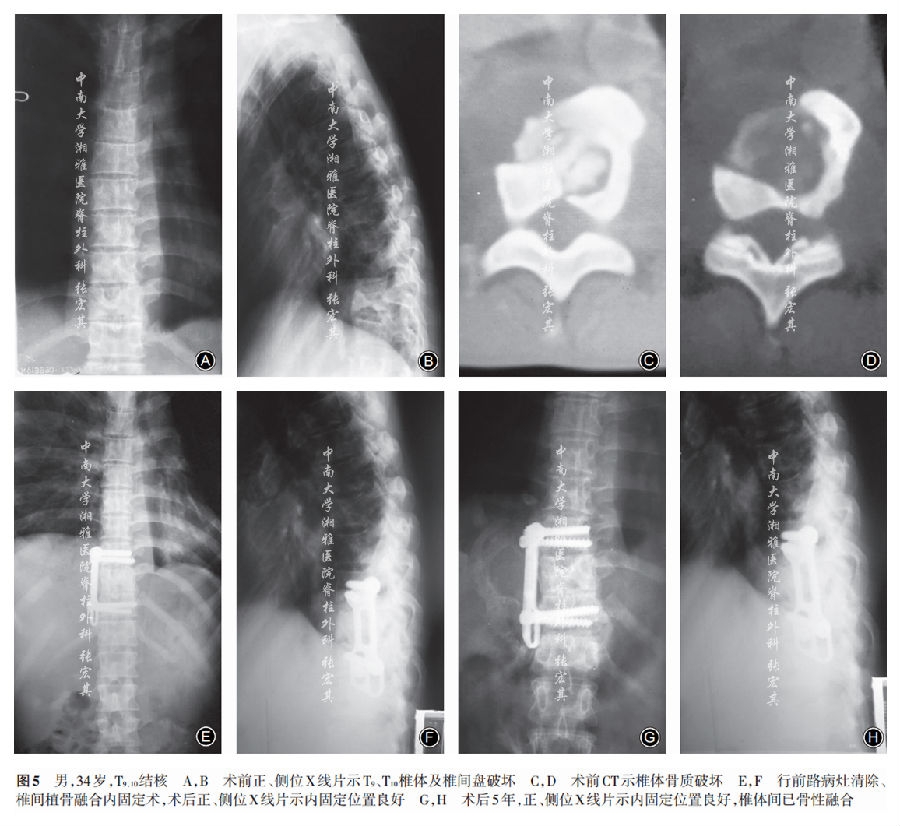

单纯前路组手术平均时间(343.65±24.74)min,出血量(965.35±122.59)ml,卧床时间(8.15±1.23)d;术后节段后凸Cobb角为13.98° ±1.73°,矫正率44.95%±16.84%(表3,图5)。术后1例由ASIA B级恢复至C级,2例由C级恢复至D级,12例由D级恢复至正常(表2)。术后3个月红细胞沉降率、C反应蛋白恢复至正常。

单纯前路组随访时间(73.6±4.5)个月,骨性融合时间(7.73±1.02)个月,末次随访时VAS评分(0.95±0.68)分,节段后凸Cobb角16.39°±1.59°,较术后即刻丢失2.80°±1.29°(表4,图5)。至末次随访时神经功能改善率为91.3%(表2)。